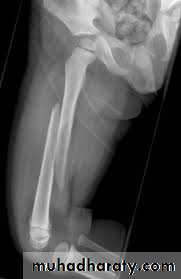

Femoral shaft fracture

This fracture occurs at any age, it is common especially in young adults, and usually results from a high energy injury, such as

( car accident , fall from height).

Most fractures have some degrees of comminuation (small fragment, single large butter fly, extensive comminuation).

X-ray :

Shows the type of fractures, and displacement. The x-ray should include the hip and knee and x-ray of pelvis to avoid missing segmental fractures, knee injuries, fractures of neck of femur, dislocation of hip, fractures of acetabulum and pelvis.

Emergency treatment :

Traction with a splint (Thomas’ splint) is first aid for a patient with a femoral shaft fracture, Shock treatment, and early transport to hospital.Thomas splint

Open fractures treated by debridement and external fixation.

Definitive treatment

closed fractures: by Open reduction and internal fixation, this will decrease the systemic complications..

Fixation of femoral shaft fracture